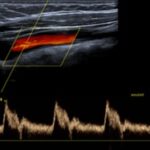

En las Imágenes A y B se valoran las arterias del eje carotídeo, presentando carótida común, externa e interna: flujos anterógrados laminares conservados con velocimetría conservada.